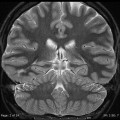

Sclérose hippocampique

• Sclérose de la corne d’Ammon =  sclérose temporale mésiale

• Sémiologie

• Perte des digitations de la tête de l’hippocampe (seul signe au début)

• Atrophie (perte hauteur)

• Gliose (hyper T2/FLAIR)

• +/- Atrophie du Gyrus ParaHippocampique (GPH)

• +/- Atteinte du pole temporal avec HS (ne modifie pas le pronostic post-op)

• +/- Atrophie fornix et corps mamillaire du côté atteinte (atteinte associée du système limbique)

• +/- Dilatation réactionnelle corne temporale

• DDX : malrotation hippocampique

MALROTATION HIPPOCAMPIQUE

• Aspect globuleux et position trop médiale de l’hippocampe

• Verticalisation du sillon collatéral plus profond